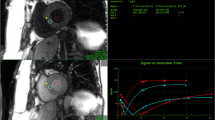

A sample T1 saturation recovery curve from a single segment as indicated, is shown in Figure 1. Figure 2 shows a representative example of best-fit baseline and post-contrast myocardial and blood T1 values, with the 18 segment format shown in A) and C), and with corresponding T1 pixel maps in B) and D). Figures 2E) and 2F) show the calculated ECV for this representative example in the18 segment and pixel map formats. Pixel formats are shown here for illustrative purposes. Average baseline T1 values (1155.3 ± 56.5 ms) were similar to previous reports using the same method [12, 13]. The ECV (20.7 ± 3.6%) was comparable to previous studies in younger adults [14]. Females showed increased non-contrast T1 (1191.7 ± 50.0 ms vs 1122.8 ± 37.9 ms) and ECV (23.0 ± 3.7% vs 18.7 ± 3.1%) compared to males.

T 1 and ECV mapping analysis in a representative subject. A) and B) show the baseline T1 values in the 18 segment model and the corresponding pixel map, respectively. The reference right ventricular insertion point is indicated by the arrow. Similar results for post-contrast T1 values are shown in C) and D), as well as for the calculated extracellular volume fraction, in E) and F).